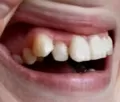

Мне 24 года. С 13-15 лет носила брекеты. В 19 прорезались зубы мудрости, и зубы верхней челюсти стали выступать из зубного ряда. Мучиться с брекетами больше не хочу.

Подскажите, есть ли ещё варианты исправления такой ситуации как у меня, хотя бы эстетически? Может виниры или элайнеры какие?

Конечно нельзя, проблема, действительно, связана с восьмыми зубами, которые необходимо удалить как можно раньше и после обратиться к ортодонту. К сожалению, выпирающий зуб настолько вылез из зубного ряда, что даже обточка и установка коронки в Вашем случае не дадут хороших результатов, да это и неправильно.

Так что выход один, хотите Вы или нет — брекеты!